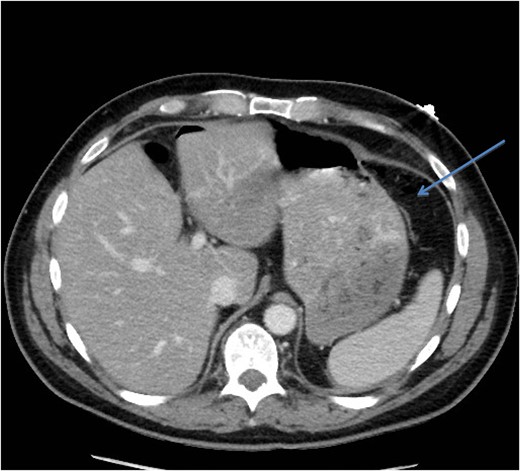

A CT scan demonstrated significant soft tissue stranding/edema of the omentum in the left hemi-abdomen. In addition, there was mild ascites and multiple scattered locules of air (Figs 3–5). No other abnormality of the small or large bowel was identified. He was admitted for observation and broad-spectrum antibiotic therapy was initiated. On post admission day 2, he became diffusely peritonitic, febrile with a temperature of 39.1°C and his oxygen requirements increased to 12 l/min.

CT scan (axial image) demonstrating gas within the omentum (arrow).

Our case demonstrates the diagnostic dilemma that accompanies delayed bowel injuries. Laboratory tests often give nonspecific results that seldom point to a diagnosis [1]. Imaging studies also fail to establish the etiology. Our CT scan failed to demonstrate significant intraperitoneal free air (Figs 3–5). In addition, oral contrast was utilized, but gross extravasation was not identified.